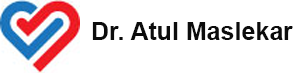

Conduits Used for Bypass grafting

Bypass Grafts